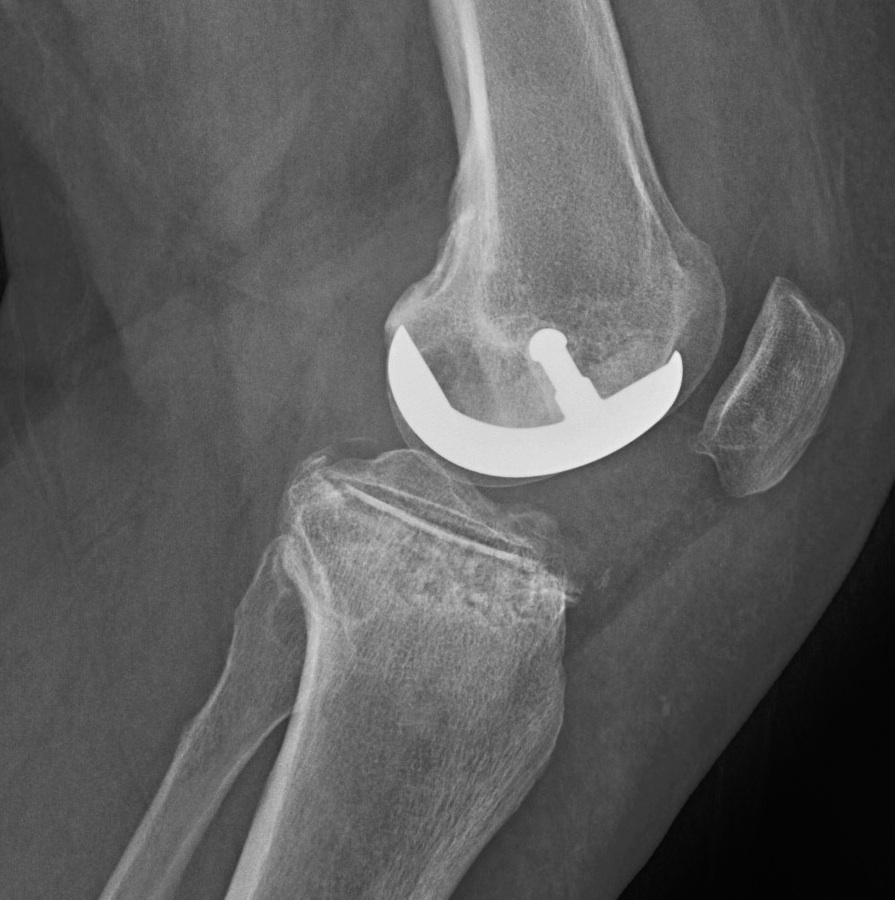

Patient 1